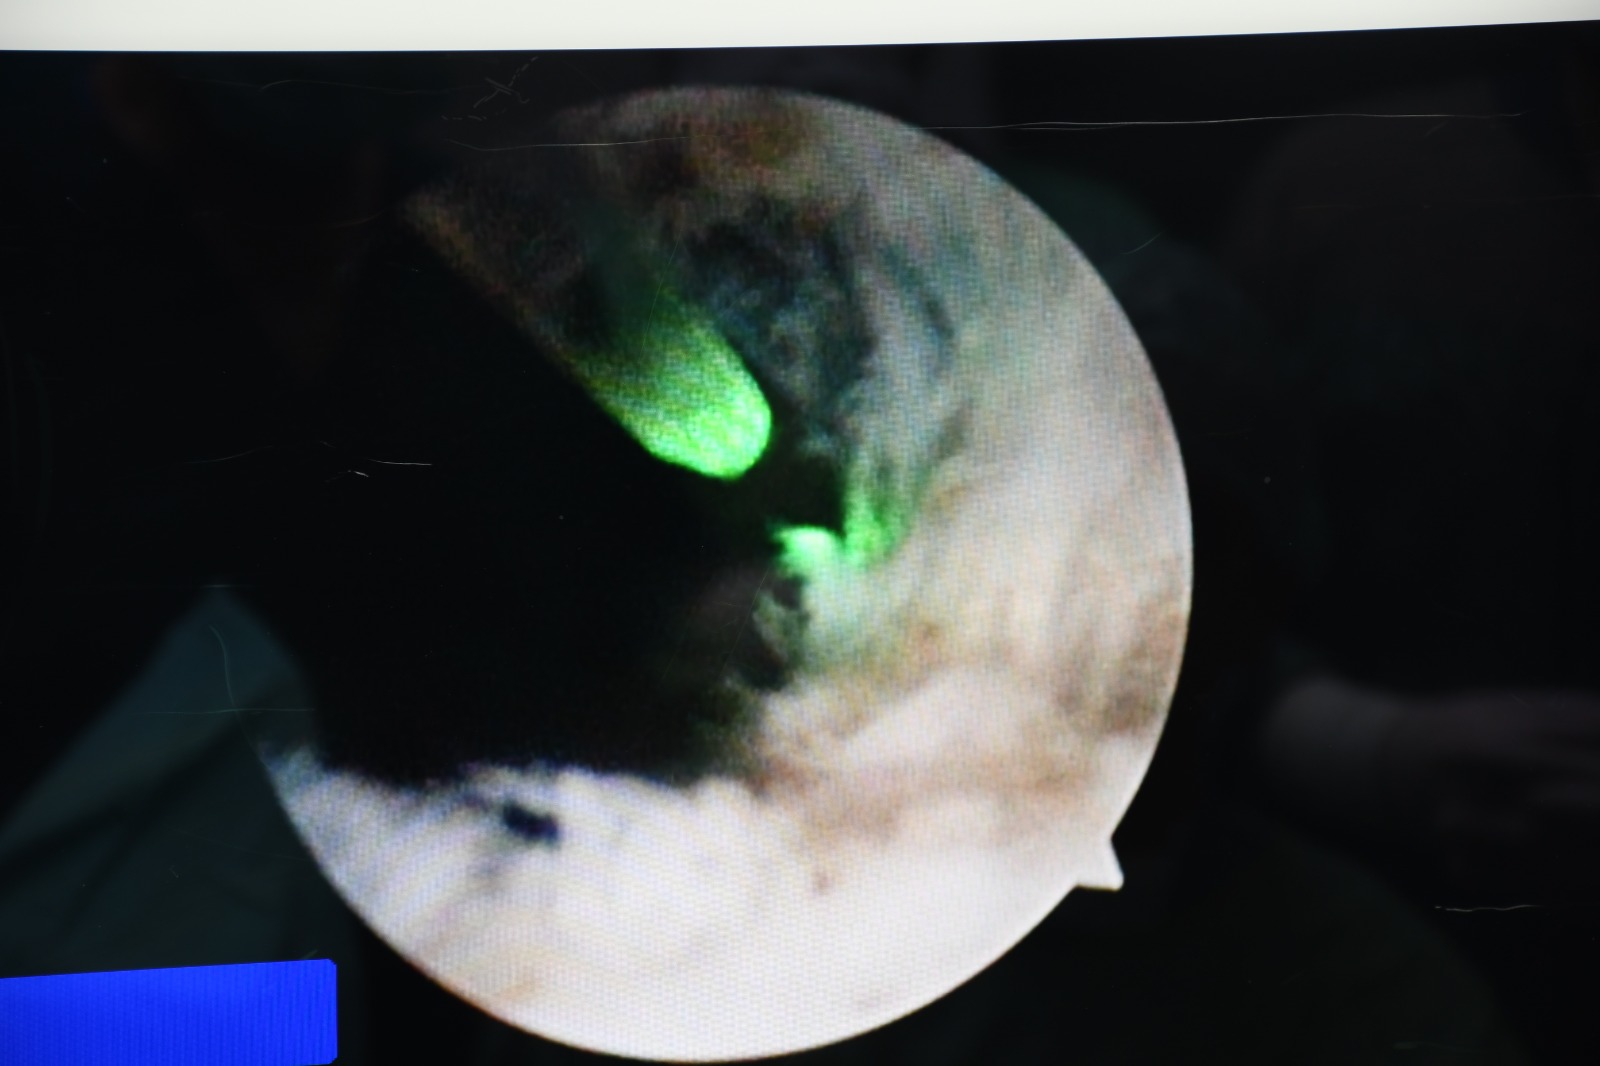

Hitit Üniversitesi Çorum Erol Olçok Eğitim ve Araştırma Hastanesi’nde ilk kez “HoLEP” (Holmium Lazerle Prostat Ameliyatı) yöntemiyle prostat ameliyatı gerçekleştirildi. Üroloji Kliniği tarafından alanında uzman hekimlerce yapılan operasyon başarıyla tamamlanırken, hasta sağlığına kavuştu.

HoLEP (Holmium Lazer Enükleasyon Prostat), iyi huylu prostat büyümesi (BPH) tedavisinde uygulanan kapalı (kesi yapılmadan) bir lazer ameliyatı yöntemidir.